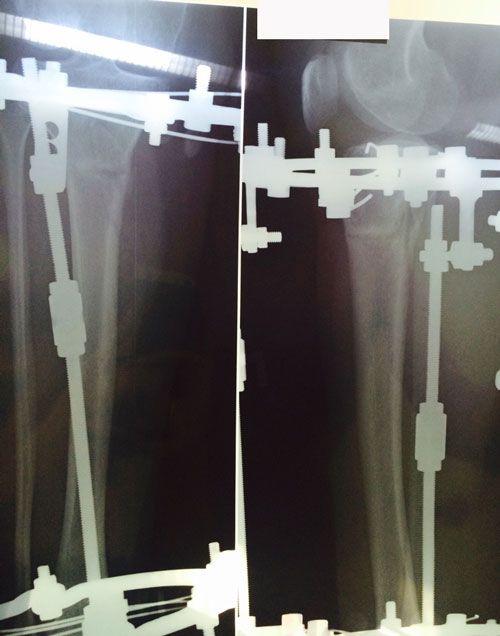

рентген в 90 дней.

Здравствуйте, Б.! Сращение идёт хорошо, но Вам ходить ещё месяц. в 120 дней ждём рентген.